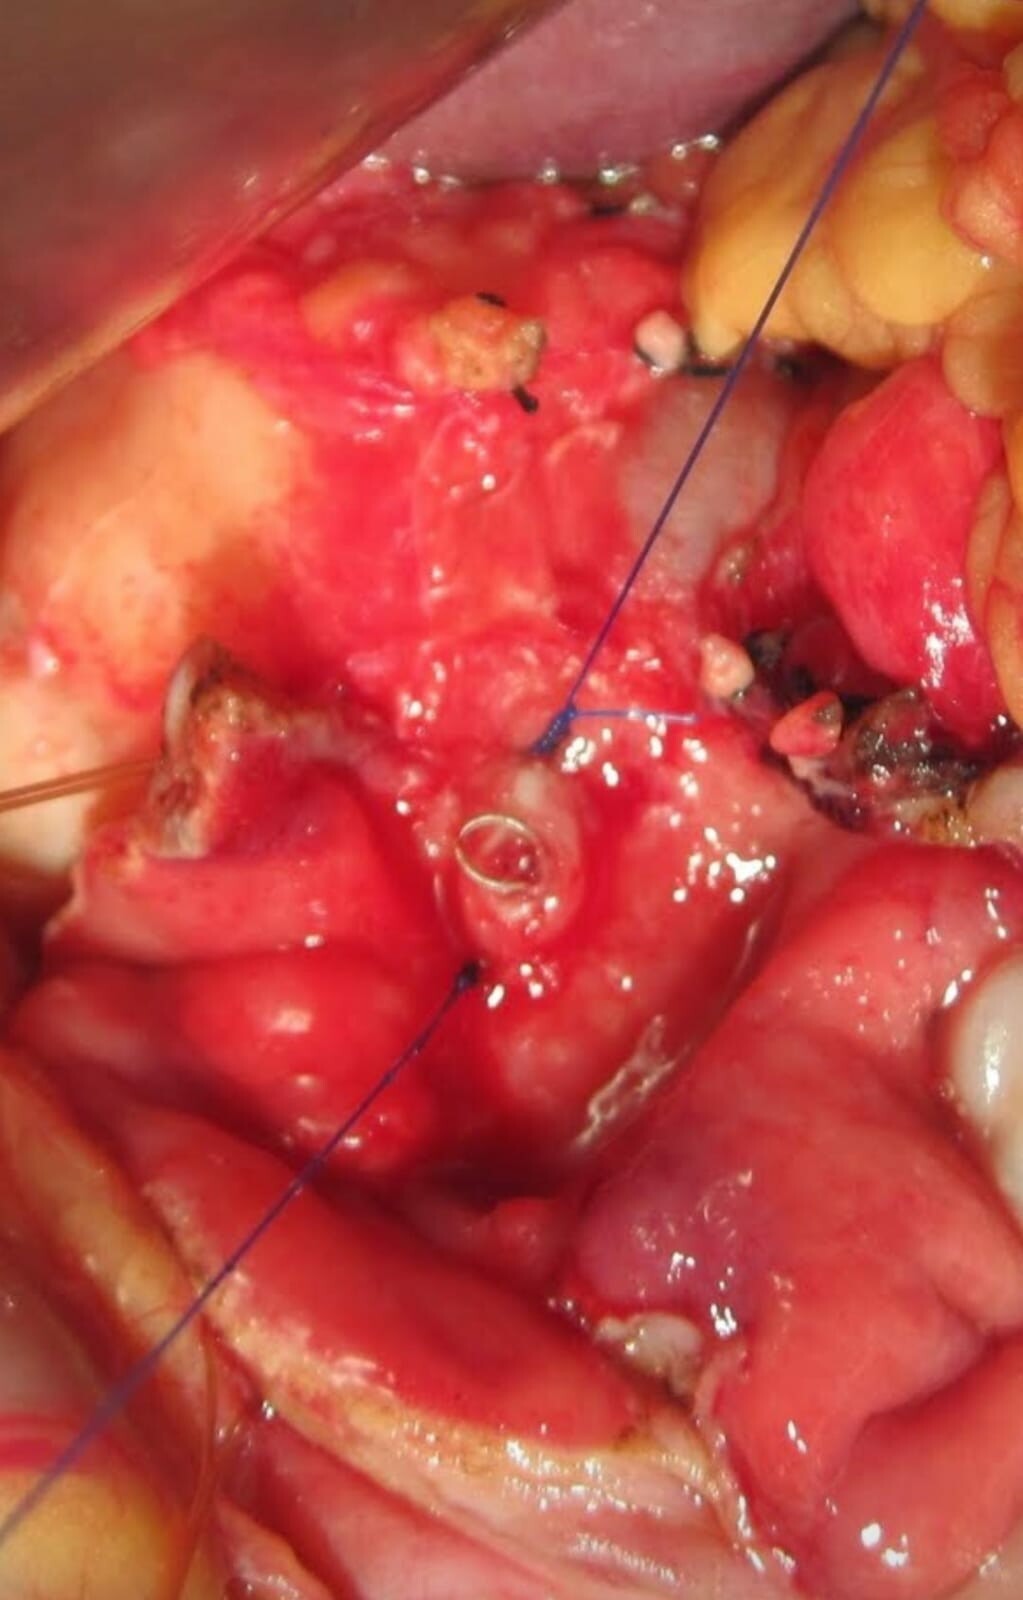

Case Summary Case Title: Chronic Calcific Pancreatitis Surgery Performed: Frey’s Procedure (Pancreatic Head Resection with Lateral Pancreaticoj...